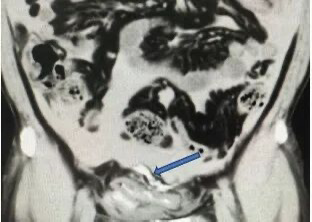

箭头处可见外渗进腹腔的造影剂

近日 广州一名年轻患者张先生(化名) 因剧烈腹痛、无法排尿紧急就医 经诊断,张先生的膀胱破裂 若不及时救治 可能引发严重感染甚至危及生命 据张先生回忆,事发当天下午他曾与好友相约了一场“拳局”,期间未规范佩戴护具,下腹部被击中后出现短暂腹痛,当时并未在意。当晚他与朋友聚餐饮酒,酒过三巡后突然感到下腹部剧烈疼痛,且无法排尿。忍痛数小时后,症状仍未缓解,最终拨打120急救电话紧急送至番禺二院。 急诊团队迅速为张先生实施导尿并进行腹部CT检查,同时联系泌尿外科团队进行病例讨论。影像结果显示,本应存在于膀胱内的造影剂竟出现于腹腔中,结合患者腹部受击打、大量饮酒后长时间憋尿的病史,确诊为膀胱破裂。 {jz:field.toptypename/}

“必须立即手术,否则尿液持续渗入腹腔,会导致感染性腹膜炎、脓毒症,危及生命。”取得患者及家属同意后,张先生被紧急送入手术室,行腹腔镜下膀胱破裂修补术。 术中发现其膀胱顶部有一长约5厘米的破口,腹腔内积存约1500毫升血性液体,肠道已被从膀胱流出的尿液浸泡。医疗团队迅速完成修补,手术顺利进行。